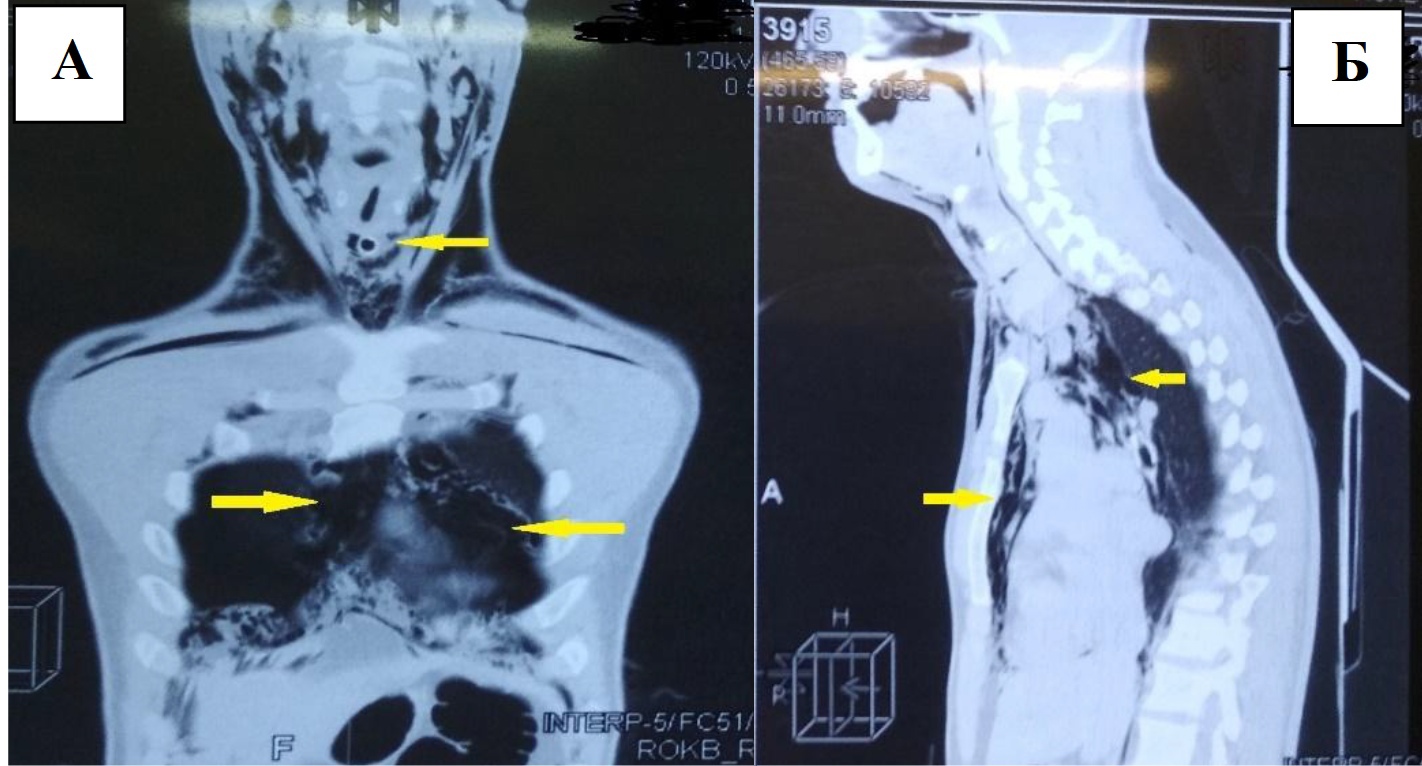

X-ray computed tomography (X-ray CT) was performed: parietal pneumothorax on both sides, pneumomediastinum, injury of the larynx, emphysema of the soft tissues of the neck and the chest wall (Figure 1).

Fig. 1. X-ray computed tomography of chest organs, frontal (A), and sagittal (B) projections. Em-physema of soft tissues of the neck, of the chest, is determined (pointed to by arrows). The tra-cheostomy tube is visualized